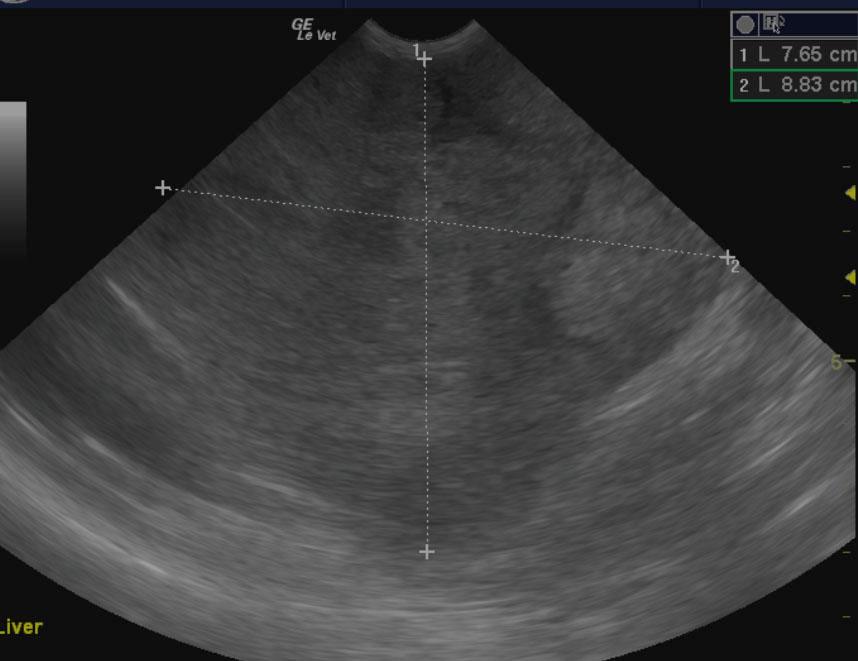

The liver in this patient presented an 8.8 x 7.6 cm, mixed, hyperechoic nodular mass with areas of capsular expansion and reactive surrounding omentum. Microaccumulation of fluid was noted within the mass as well. It appeared to derive from the left liver and extend into the deep left liver enveloping the cranial aspect of the gallbladder and separate nodular changes were noted in the right liver in the region from the vena cava inlet through the diaphragm. Loss of architecture was noted throughout this region. The gallbladder revealed a minor amount of dependent debris. The mass appeared to impinge upon the portal vein from the left side with nodular changes on the right side are suspected as well.